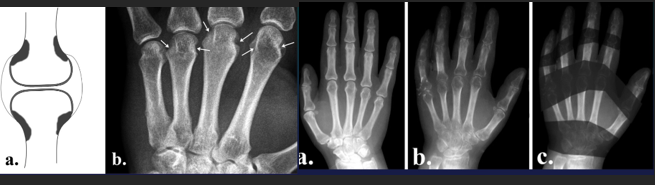

RA

CharaK RA hands

Focal soft tissue swelling

early=> MCPh, PIPh, ulnar styloid

OP

early=> juxtaarticular, band

late=> diffuse

Erosions

early=> decreased cortical differentiation (dot dash pattern)

marginal = moue ears at basis of the phalanges

subchondral=> pen in cup, destruction of ulna, carpal bones

Cartilage destruction

early false increased of joint space (effusion)

destruction & narrowing of joint space

Subchondral cysts

Malalignement

carpal: ulnar deviation and scaphoid luxation

fingers: MCPh, ulnar deviation, subluxation

RA hand joints

Dg CLUES

Purely erosive

Joint alignement changes

LOC

Classic: symétrie (+ unilateral in early stages)

Early: MCPh, distal RU, RC

Late: PIPh, IC

Almost NEVER involved DIPh